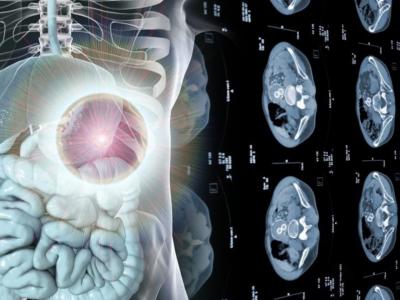

Tumor operation girl : सिटी स्कॅन करून पाहिलं तेव्हा कळलं की रुग्णाच्या संपूर्ण शरीरात मोठा ट्यूमर होता. ज्याचा आकार 30x20x14 सेंटीमीटर होता, म्हणजेच दोन मोठ्या फुटबॉलप्रमाणे या ट्यूमरचा आकार होता.

सुज आलेली नाही तरीही या मुलीचं पोट एव्हढं फुगलेलं होतं. त्यानंतर आम्ही सिटी स्कॅन करून पाहिलं तेव्हा कळलं की रुग्णाच्या संपूर्ण शरीरात मोठा ट्यूमर होता. ज्याचा आकार 30x20x14 सेंटीमीटर होता, म्हणजेच दोन मोठ्या फुटबॉलप्रमाणे या ट्यूमरचा आकार होता. हा ट्यूमर काढण्यासाठी सर्जरीशिवाय कोणताही दुसरा पर्याय नव्हता.

ऑपरेशनदरम्यान पोटात मोठा ट्यूमर दिसून आला. रक्त, नसा आणि शरीराच्या इतर भागांमध्येही हा ट्यूमर वाढत जात होता.